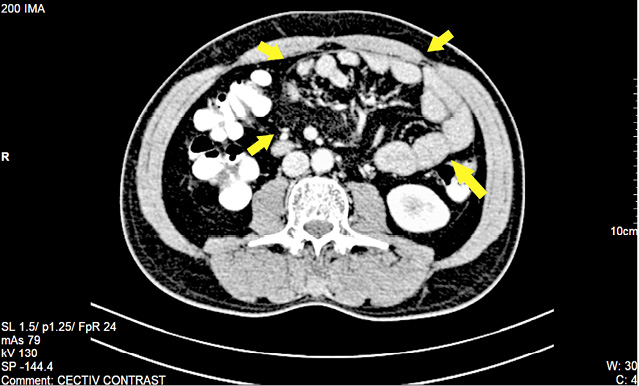

We present a case of a 62-year-old man who presented to the surgical emergency department with complaints of distension of the abdomen and inability to pass stool or gas for 48 hours. He also had three episodes of bilious vomiting. On clinical examination, there was tachycardia and signs of dehydration. The abdomen was distended with absent bowel sounds. He was admitted and started on parenteral intravenous fluid resuscitation. All investigations including hematology and biochemistry were normal. Chest radiograph with both domes of the diaphragm was normal. An abdominal radiograph revealed multiple air-fluid levels suggestive of small bowel obstruction. A contrast-enhanced CT scan of the abdomen revealed dilatation of proximal ileal and jejunal loops with abruptly cut off at the level of the proximal-mid ileal loop. There was circumferential thickening of proximal-mid ileal loops. There was twisting of distal jejunal and proximal ileal loops along with a defect in the mesentery at the level of umbilicus likely to be a small bowel trans mesenteric internal hernia (Figures 1, 2). Abdominal Tuberculosis workup was done with Polymerase Chain Reaction (PCR) for mycobacterium, manteaux test and Cartridge Based Nucleic Acid Amplification Test (CB-NAAT) Sputum were negative. He was managed conservatively with nasogastric decompression with a nasogastric tube, intravenous fluids, and symptomatic drugs. There was partial relief of obstruction after the second day of admission.

Clinical diagnosis is difficult because of non-specific symptoms. Plain radiographs of the abdomen may reveal nonspecific bowel loop dilatation and air-fluid levels. Ultrasound abdomen may reveal a cauliflower or a trilaminar appearance of the bowel. CT has facilitated accurate preoperative diagnosis, long before the patient presents with full-fledged symptoms of acute intestinal obstruction. CT scan is the imaging of choice and plays a significant role in excluding the secondary causes and helps in patient management. The identification of thickened contrast-enhanced peritoneal membrane with encapsulated bowel loops called “cauliflower sign” is a significant finding. CT also helps in identifying the cause and delineating the complications [4–6].